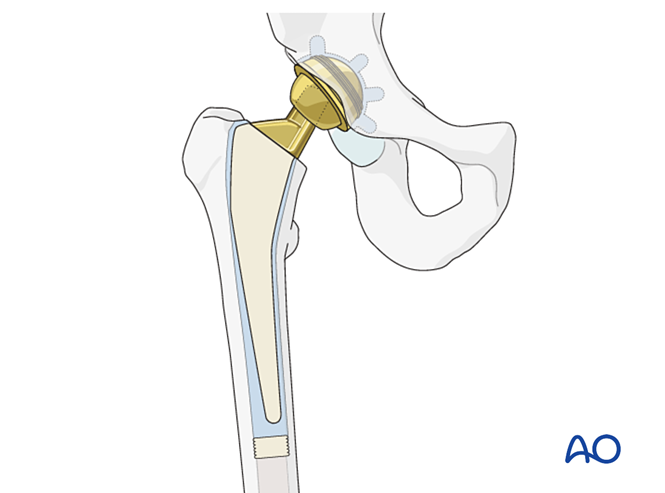

假体置入与冠状面对位

目标:假体柄中立位置入股骨髓腔。避免因偏心力致假体颈内翻。

图示骨水泥柄正确对位(左)与内翻对位(右,易致松动)。

假体组装用试模头确认颈长(影响下肢长度、软组织张力及髋稳定性)。复位后检查活动度及稳定性,评估:●髋关节在轻度内收、内旋、屈曲或过伸时是否半脱位/脱位?●假体颈长及偏距是否与术前健侧模板匹配?(股骨头旋转中心是否恢复?)●假体前倾角是否适当?●后关节囊及外旋短肌能否复位至股骨近端止点?

确认后安装最终股骨头。